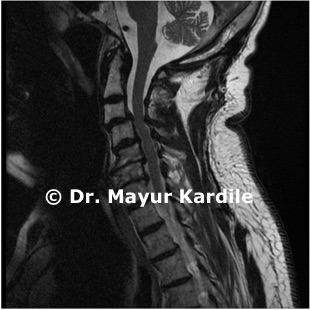

Cervical Myelopathy

65 yr gentleman